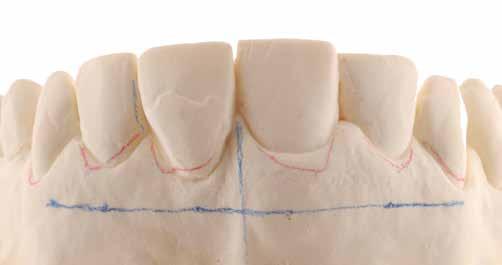

Az előzetes állapotfelmérést és a kezelés megtervezését követően a fogakat minimál invazív módon preparáltuk (1. a-b ábrák), majd az előkészített fogak ínybarázdáiba fonalbehelyező eszköz segítségével (113 Serrated Gingival Cord Packer, Hu-Friedy, Chicago, Illinois) teflonszalagot helyeztünk (Loctite Thread Seal Tape, Henkel Loctite Corp., Egyesült Államok), (1. c ábra). A hagyományos retrakciós fonalak helyett, a rugalmasságuk miatt előnyösebbnek tartjuk a teflonszalagok használatát. A kofferdámot (Dental Dam, Nic Tone, Bukarest, Románia) az előkészített fogakon kívül, az azoktól disztálisan elhelyezkedő egy-egy fognak megfelelően is perforáltuk.

gével finoman az ínybarázdába fordítjuk (2. c ábra). Azokra a fogakra, amelyekre aktuálisan héjakat akartunk helyezni, ezen felül kiegészítő kapcsokat is helyeztünk (Hygenic Brinker Clamp #B4, Coltene/Whaledent Inc., Cuyahoga Falls, Ohio, Egyesült Államok), (2. d ábra) Ebben a stádiumban érdemes a héjakat még bármilyen ragasztóanyag vagy próbapaszta nélkül a helyükre illeszteni (dry tryin). Erre azért volt szükség, hogy még a tényleges ragasztási folyamat megkezdése előtt ellenőrizni tudjuk a restaurátum és a fog pontos illeszkedését, valamint a széli záródási vonalhoz való akadálytalan hozzáférést (3. a ábra). Ideális esetben a héjak felhelyezését párosával, a középvonaltól disztál felé haladva végezzük. Ennek megfelelően a jobb (1.1) és bal felső nagymetszőfogakra (2.1) kapcsokat helyeztünk, majd a szomszédos fogakat teflonszalag segítségével izoláltuk. Ezt követően az 1.1-es és 2.1-es fogak héjak elhorgonyzására szolgáló felszíneit 32%os foszforsavval (Uni-Etch w/BAC, Bisco Dental, Schaumburg, Illinois, Egyesült Államok) 30 másodpercen keresztül kondicionáltuk. Ez után a felszínek vízzel történő lemosása és óvatosan

leszárítása következett (3. b ábra). A fogfelszínek előkészítésének utolsó lépéseként a primert és az adhezívet (OptiBond FL, Kerr Dental Orange, Kalifornia, Egyesült Államok) a gyártói javaslatnak megfelelően a felszínekre applikáltuk, majd 20 másodpercen keresztül polimerizációs lámpával világítottuk (Valo LED Curing Light, Ultradent Products Inc., South Jordan, Utah). Az 1.1-es és 2.1-es fogakat borító héjak ragasztása során világos színű, fényre kötő ragasztócementet (Variolink Esthetic LC, Ivoclar Vivadent, Schaan, Liechtenstein) alkalmaztunk. A ragasztóanyagot először a héjak belső felszínére vittük fel, majd ezeket az előkészített fogfelszínekre helyeztük (3. c ábra). Az approximális felszíneken megjelenő cementfelesleget egy ecset (Profi Natural Bristle Brush, Renfert, Hilzingen, Németország) és fogselyem (Oral-B Glide Pro-Health Deep Clean Floss, Procter & Gamble, Cincinnati, Ohio, Egyesült Államok) segítségével még a ragasztóanyag megvilágítása előtt eltávolítottuk. A megvilágítás során a különböző fogfelszíneket (labiális, meziális, disztális és incizális) 20-20 másodpercen keresztül világítottuk meg (3. d ábra)